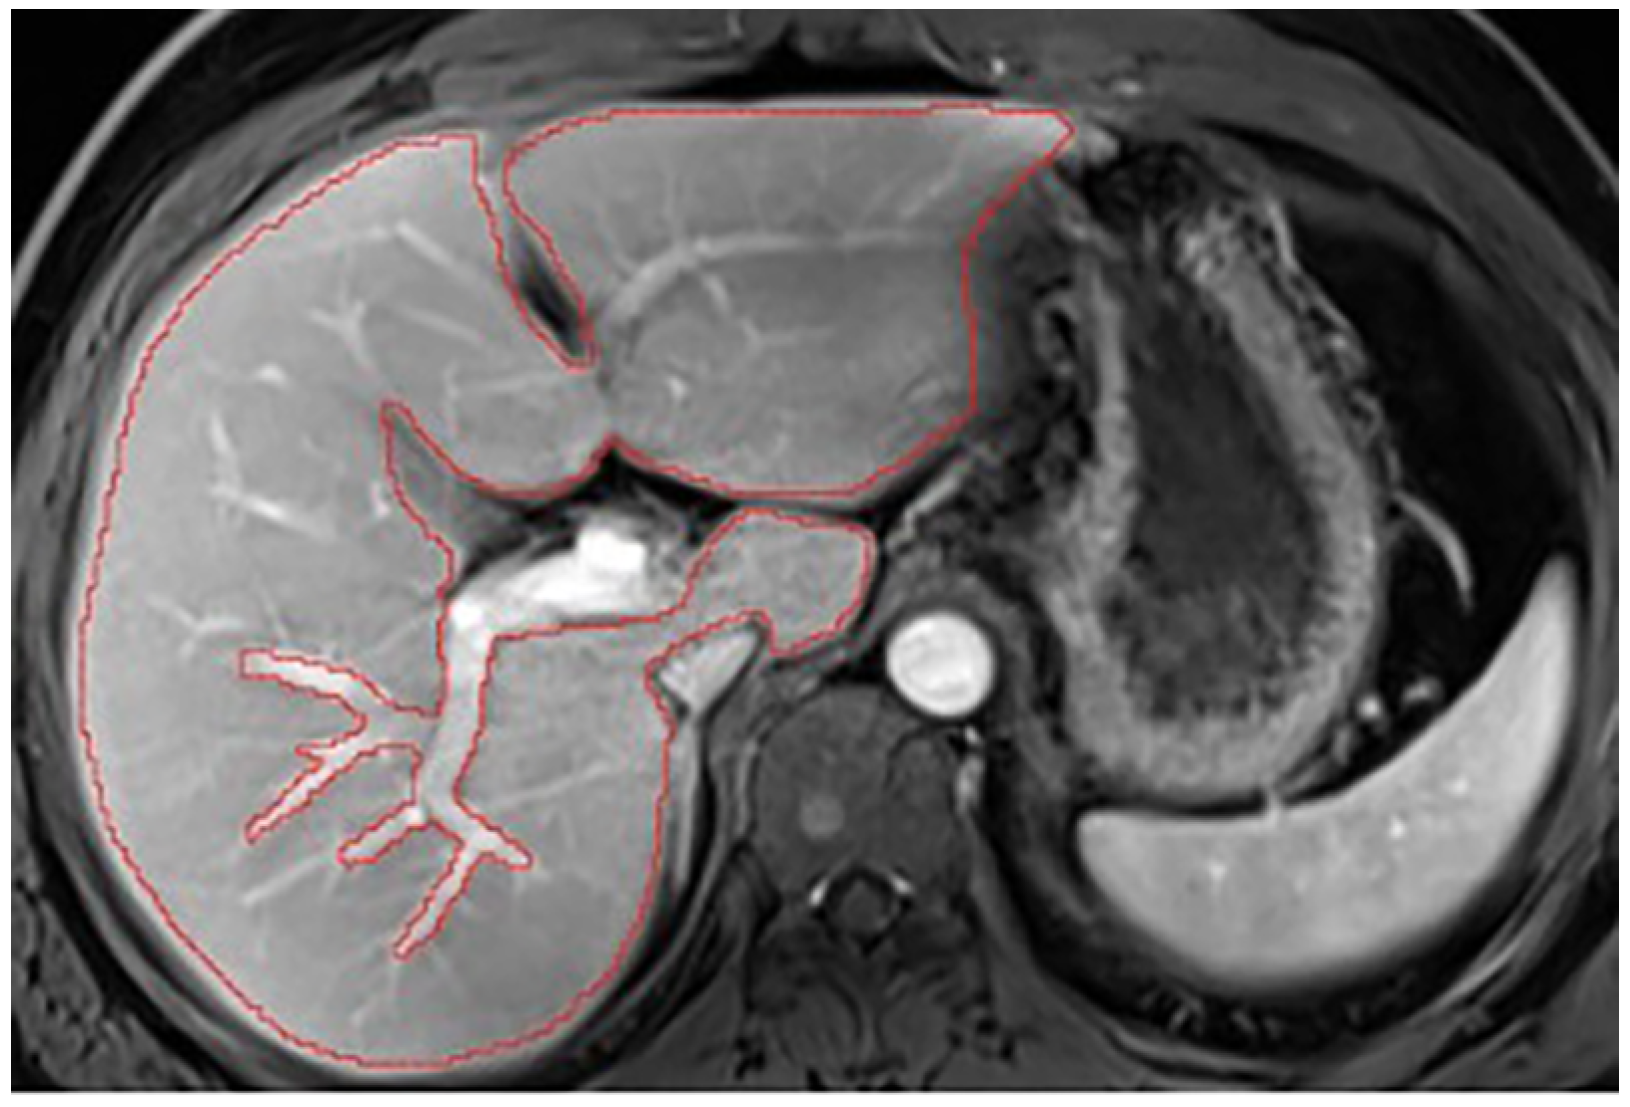

Appendix A.5. Multi-Part Liver Parenchyma